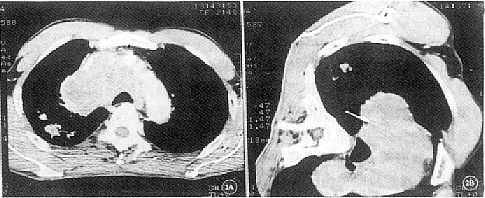

图1 左上肺结节灶,1.8 cm×2.5 cm大小,活检示小细胞低分化癌

图2 同图1病例,A,增强扫描,纵隔血管增强明显,病灶和血管关系清晰;B,实施活检时避开血管,结果同上,为肺癌纵隔淋巴结转移